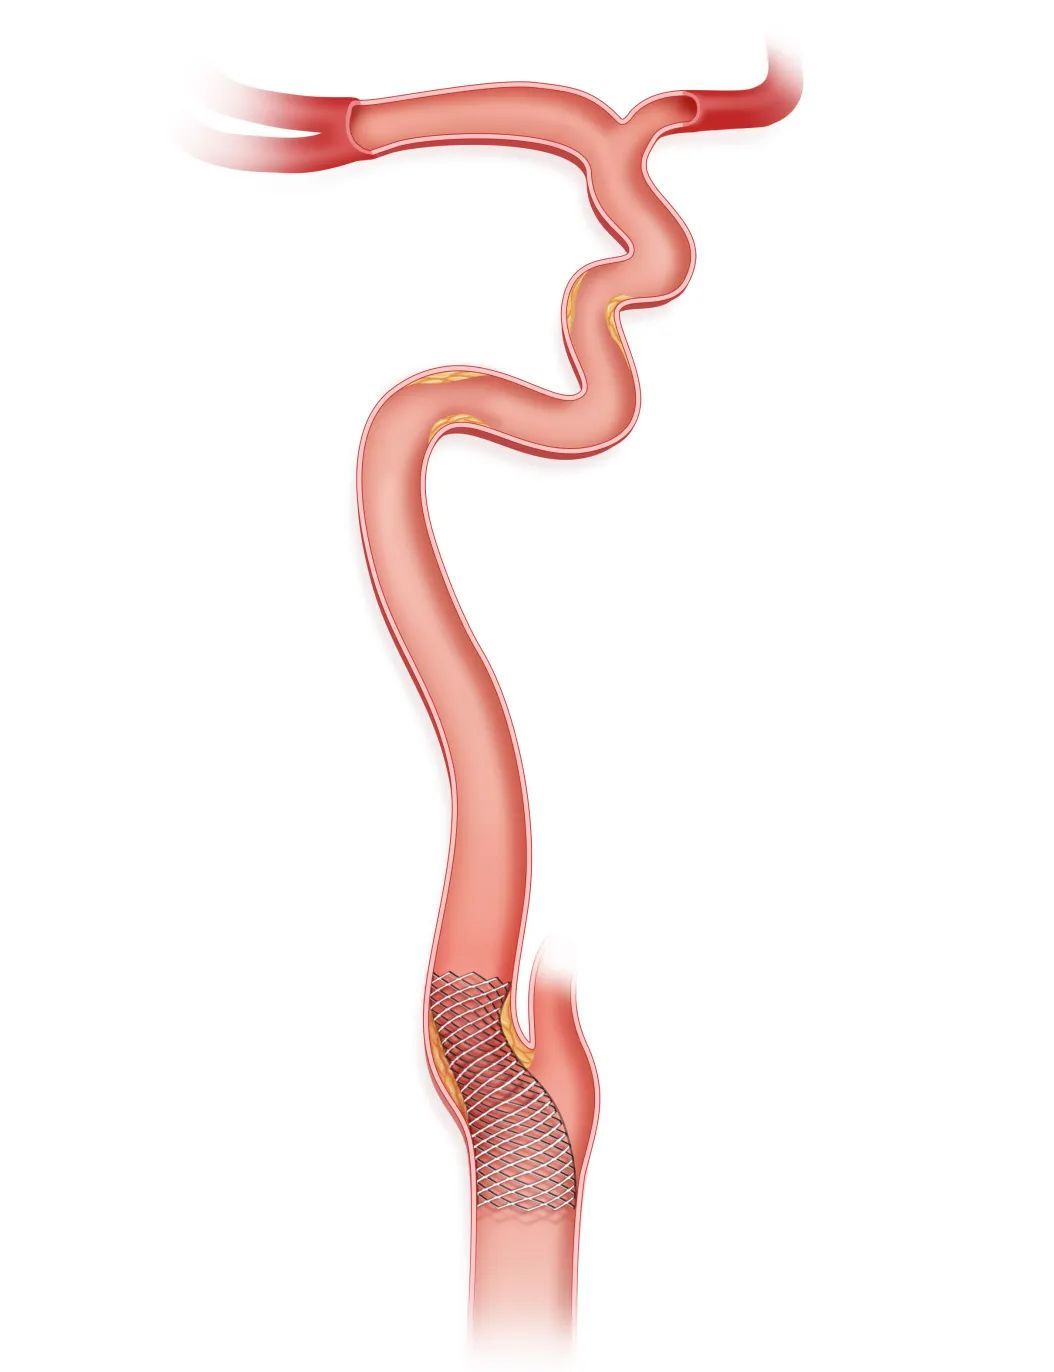

微导丝微导管突破闭塞段后,将Syphonet®取栓支架跨越M1段与颈内动脉末端释放,起到颅内远端血管的保护作用。

沿Syphonet®取栓支架输送导丝送入小直径的SacSpeed®球囊扩张导管(2mm-2.5mm),由远及近依次对可疑病变部位进行扩张,后再次足量、足压力造影,明确闭塞段内原始病变部位、继发血栓部位和假性闭塞部位。

再次释放Syphonet®取栓支架,选取合适的SacSpeed®球囊扩张导管扩张残余的严重狭窄部位。应尽量避免支架置入,在出现明显限流性夹层、斑块回缩明显限制前向血流的部位,可考虑经Syphonet®取栓支架输送导丝送入支架系统,支架释放后进行球囊后扩张以提高支架贴壁性,降低再狭窄和再闭塞率。